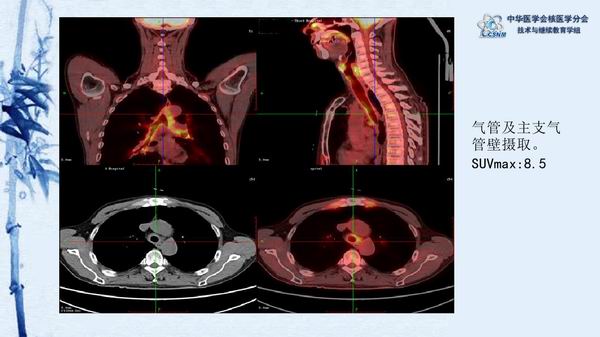

讲座15:复发性多软骨炎-张卫方